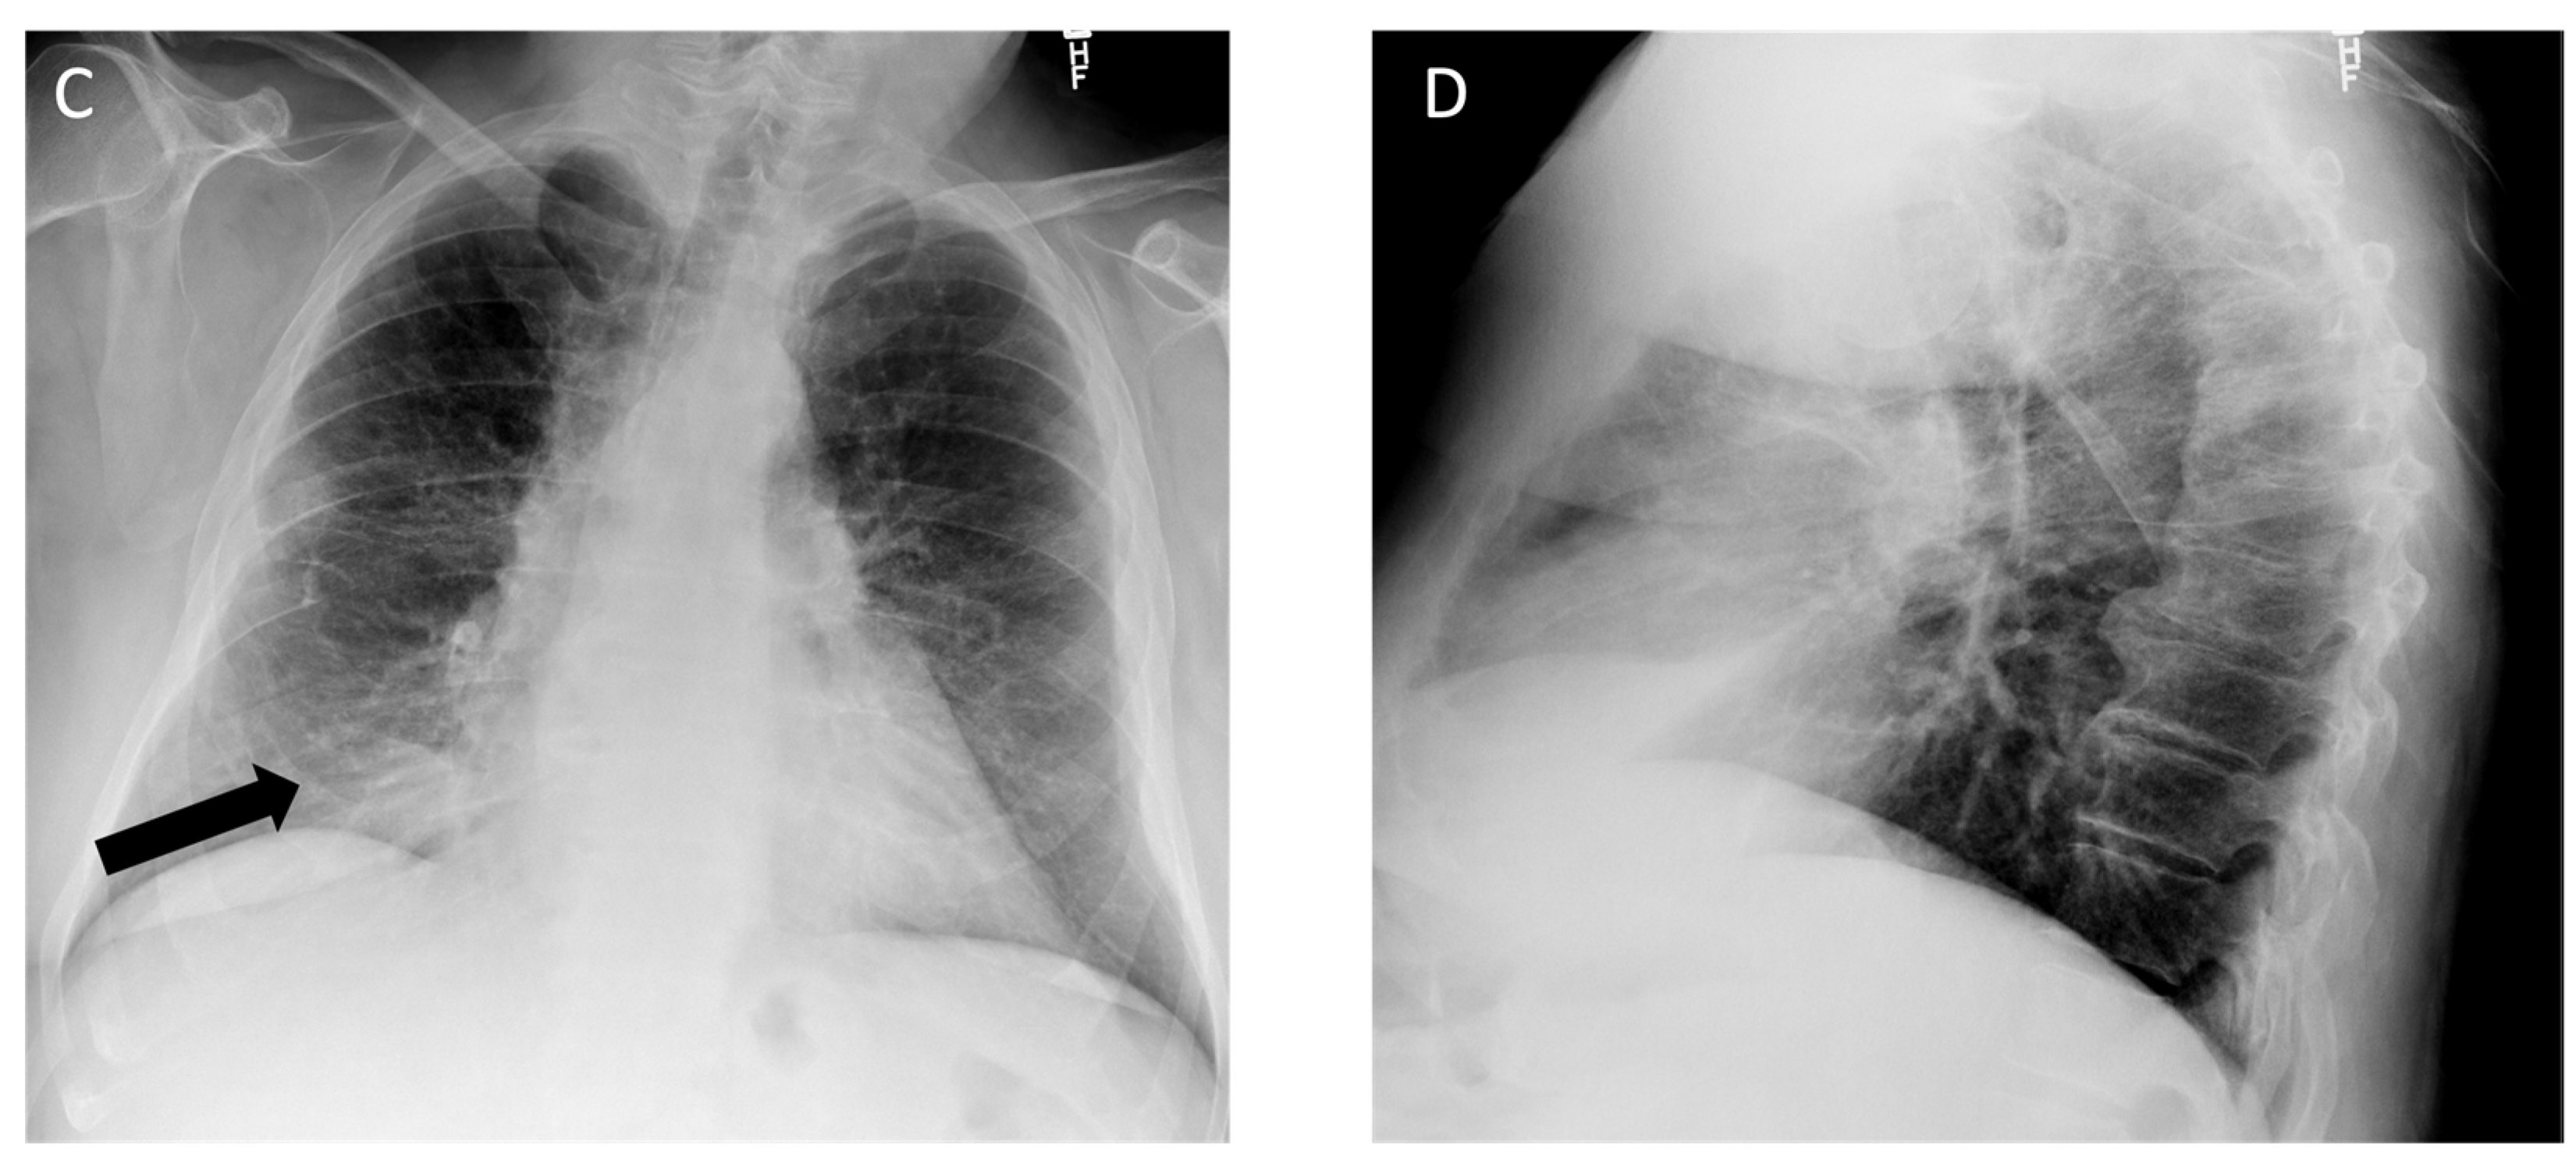

4.3. Asbestos-Related Lung Disease

| Asbestos-Related Lung Disease | Pleural effusion, smooth pleural plaques, rounded atelectasis [42,43,44] | Presence of smooth pleural plaques, often bilateral and along all pleural surfaces [45,46] |

| Mesothelioma | Various types of pleural thickening, interlobar fissure involvement, pleural effusion, pleural plaques [51] | Atypical pleural plaques, chest wall invasion [51] |